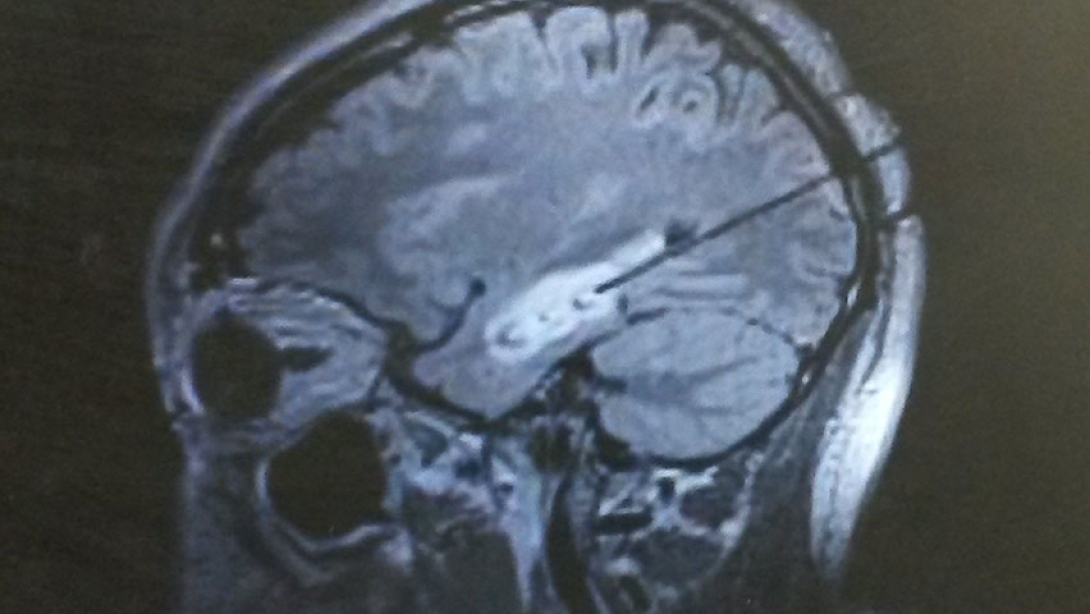

Open brain surgery for epilepsy didn't appeal to him, so the Colemans settled into this adjusted lifestyle until they learned about a newer, less invasive treatment option that's performed in an MRI suite. Called laser interstitial thermal therapy, LITT for short, it uses a beam of targeted heat to attack — and destroy — the portion of a patient's brain causing the seizures. His Michigan Medicine neurologist, Nusha Mihaylova, M.D., Ph.D., told him laser ablation allows the surgeon to remove a seizure focus with pinpoint accuracy. Preserving his memory, IQ and other brain functions so Coleman would still be able to work was essential.

Levin, an assistant professor of neurological surgery at Michigan Medicine, started planning his LITT procedure. Because all brains are different, so are all brain surgeries.

"Rob's seizures were coming from the left temporal lobe," Levin explains. "We also had to figure out where his speech and memory functions happen." She plotted a route to the source of the seizures that wouldn't damage those normal areas of Coleman's brain.

Coleman was asleep, getting MRIs throughout the day, while Levin operated on his brain for about an hour, only making an incision smaller than a quarter-inch. He was home the next day, resting for a couple of weeks, and back to work in his home office the next month.